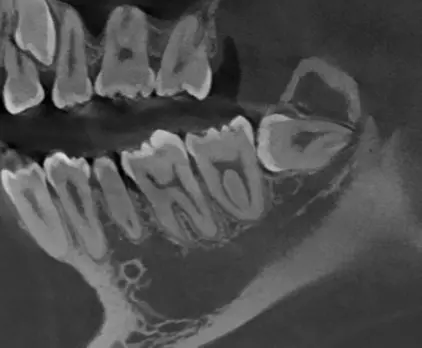

TOMOGRAFÍA DE TERCERAS MOLARES

Identifica la relación dentaria con el conducto mandibular y evitar complicaciones en el proceso quirúrgico.